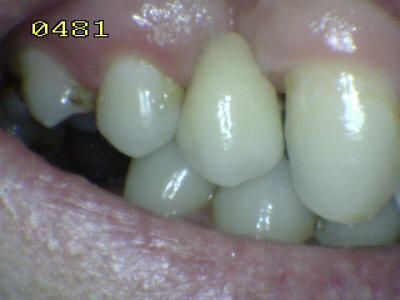

Caso finalizado